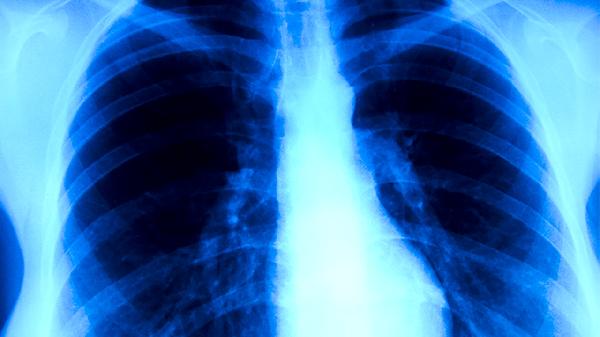

肺结核会传染给家人。肺结核属于传染病,通过呼吸道飞沫传播,若患者处于活动期且未规范治疗,与家人密切接触可能导致传播。家庭成员感染的概率与接触频率、环境通风情况及患者痰菌是否阳性等因素相关。

痰涂片阳性的肺结核患者传染性较强,咳嗽、打喷嚏或大声说话时产生的飞沫可能携带结核分枝杆菌。共同生活的家人因长期共处密闭空间,若未佩戴口罩或未及时消毒,病原体可通过吸入被污染的空气传播。患者的衣物、餐具等物品若未分开清洗消毒,也可能成为间接传播媒介。免疫力较低的老人、儿童或慢性病患者更易被感染。

痰涂片阴性的非活动性肺结核患者传染性较低,但仍有潜在传播风险。部分患者经治疗后痰菌转阴,但肺部病灶未完全钙化时,仍可能通过剧烈咳痰释放少量病原体。家中有孕妇或免疫缺陷患者时,即使患者病情稳定也需加强防护措施。接触者若出现持续咳嗽、低热或盗汗等症状,应尽早就医筛查。

建议患者居家治疗期间单独居住,保持房间每日通风2-3次,每次30分钟以上。家人接触时应佩戴医用外科口罩,患者痰液需用含氯消毒剂处理。所有家庭成员需进行结核菌素皮肤试验或干扰素释放试验筛查,儿童及密切接触者可在医生指导下预防性用药。患者需规律服用异烟肼片、利福平胶囊、吡嗪酰胺片等抗结核药物,完成全程治疗以降低传染风险。